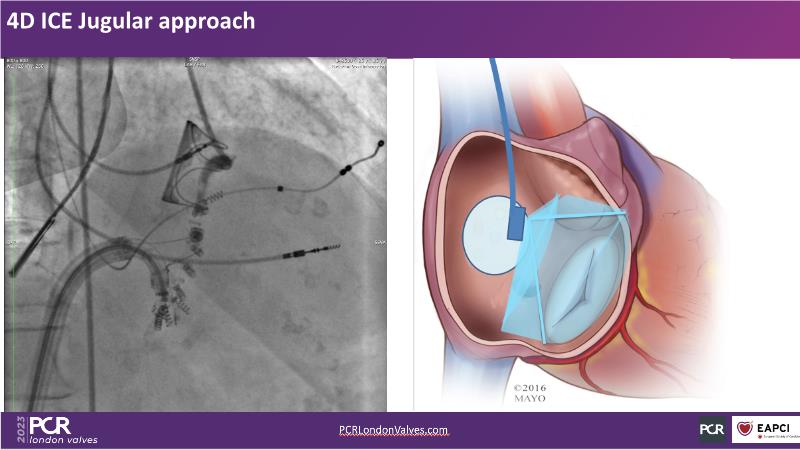

Expert roundtable: 4D ICE in tricuspid interventions

Join this session if you want to get familiar with the 4D ICE technology and the key elements of image guidance for tricuspid interventions, understand how 4D ICE can assist in specific procedural steps during challenging tricuspid interventions, and engage in an interactive discussion with experts about the current use of 4D ICE and insights into future developments.

- To get familiar with the 4D ICE technology and the key aspects of image guidance for tricuspid interventions

- To learn how 4D ICE can support specific procedural steps in challenging tricuspid interventions